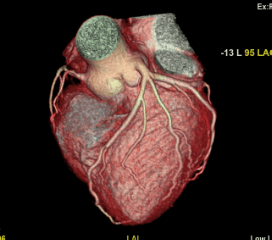

Cardiac Scan 1

Cardiac Scan 2

Cardiac Scan 3

Cardiac Scan 4

Cardiac Scan 5

Cardiac Scan 6

Cardiac Scan 7

Cardiac Scan 8

Cardiac Scan 9

Cardiac Scan 10

Cardiac Scan 11

Cardiac Scan 12

Coronary Angiogram

A CT Coronary Angiogram is a non-invasive imaging test that uses a CT scanner, and contrast dye to create detailed 3D pictures of your heart's arteries, revealing plaque, blockages, or narrowing (stenosis) that can cause heart problems like chest pain.